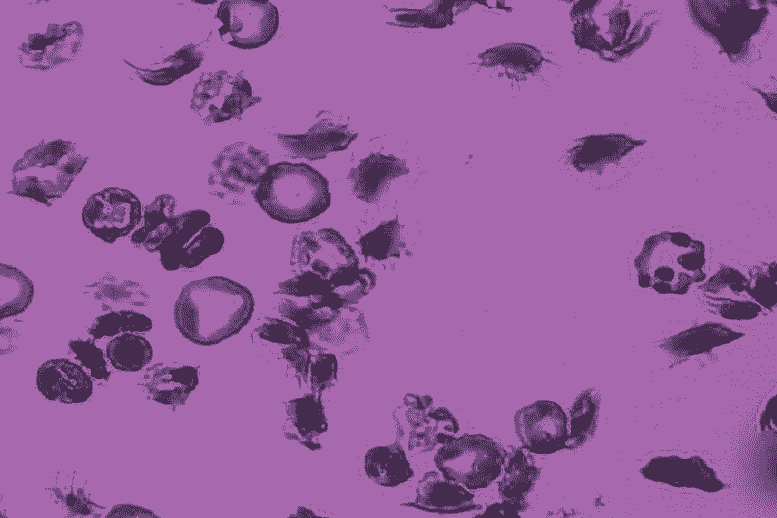

棒状杆菌(学名:棒状杆菌)是革兰氏阳性菌属,属于放线菌目棒状杆菌科。非运动、非抗酸、无芽孢杆菌。细胞是直的、弯曲的或多形的,通常是杆状的。一般不运动。好氧或兼性厌氧,化学有机营养型。进行氧化或发酵代谢。过氧化氢酶阳性。 G+Cmo1%值为51-59。

人和动物的寄生虫和病原菌:直的或微弯曲的杆菌,常呈杆状扩张,细胞突然断裂分裂形成角状、栅栏状排列;一般不动深红诺卡氏菌,不耐酸;碳水化合物代谢既有呼吸作用又有发酵作用;细胞壁含有外消旋二氨基庚二酸、阿拉伯糖和半乳糖等;需氧和兼性厌氧菌; DNA 中 G+C 摩尔含量为 52 至 68%。该部分有9个官方种,模式种为白喉棒状杆菌。

这种细菌的产生与能产生外毒素的原噬菌体有关。外毒素是由单肽组成的蛋白质,分子量为63,000;土拨鼠试验中的致死剂量为 10-7 克。经温蛋白酶处理,分为分子量为24,000的N端A片段和分子量为38,000的C端B片段。片段 A 有一个作为毒素的活性部分;片段 B 具有识别靶细胞的部分。其毒素作用机制是肽键延长因子EF-2被ADP核糖基化灭活,从而抑制蛋白质合成。它具有高度抗原性(E.A. von Behring,Shibazaburo Kitasato),其对抗毒素的反应仍在继续研究中。正在对母体免疫力及其消失(大约在出生后三年)进行实验研究,以了解毒素的致病性和希克反应的一些免疫学方面。对类毒素的使用免疫。菌体一端或两端可见异染颗粒,亚碲酸钾血琼脂平板上形成黑色菌落。

诺卡氏菌(学名:Nocardia)是诺卡氏菌属的细菌属。需氧革兰氏阳性杆菌。细菌为多形性、球形、棒状、丝状,大小为0.6×(3~4)微米,无运动性,部分菌株弱抗酸,专性好氧,营养要求一般,普通琼脂平板培养3天后可见菌落,7~10天菌落隆起,气生菌丝形成后,表面蓬松,不同品种菌落呈黄色,橙色、红色或这些色素。混合色。DNA中的G+C分子含量为60-72%。大部分是腐生菌,存在于土壤中。有星形细胞瘤诺卡氏菌、巴西诺卡氏菌、诺卡氏菌4种mallei 和 Nocardia 豚鼠,